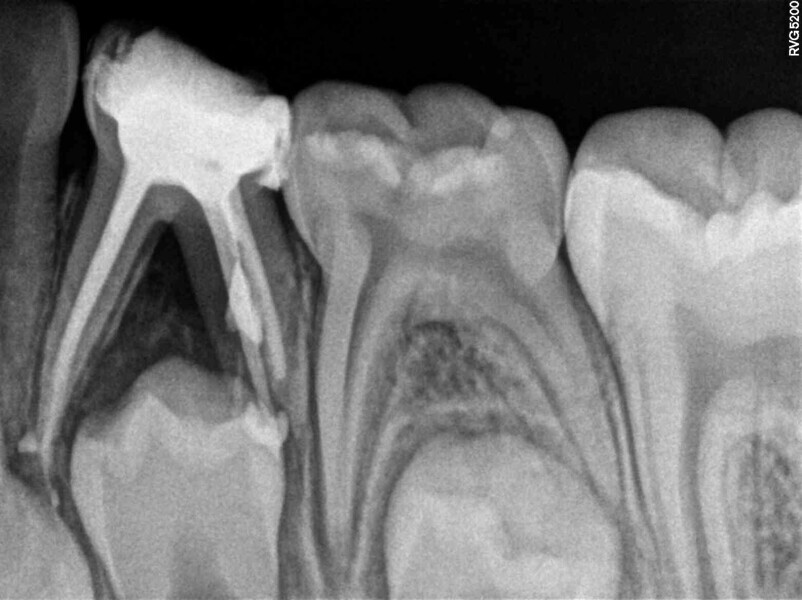

Cas 2 (Figs. 5 à 9)

Ce patient âgé de 6 ans et 7 mois présentait une carie dentaire à un stade avancé sur la première molaire temporaire inférieure gauche, sans aucun symptôme de douleur. La percussion et la palpation du versant vestibulaire de la gencive occasionnaient une légère gêne. Un abcès était présent, mais aucune mobilité dentaire n’était observée. La radiographie a révélé une zone importante de perte osseuse inter-radiculaire. Un diagnostic de nécrose pulpaire et d’abcès apical asymptomatique a été établi. Une pulpectomie a été réalisée et, au cours d’un second rendez-vous qui a permis de confirmer l’absence de signes ou de symptômes pathologiques, une couronne en acier inoxydable a été mise en place. La visite de rappel effectuée à 14 mois a montré l’absence de toute pathologie clinique et l’évolution normale du processus éruptif des prémolaires permanentes, malgré l’extrusion du matériau d’obturation.